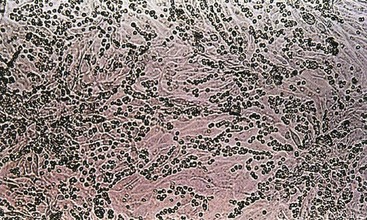

Many viruses produce a characteristic CPE. Characteristic CPEs in the tissue sample or in cell culture include changes in cell morphology, cell lysis, vacuolation, syncytia (Figure 47-1), and inclusion bodies. Syncytia are multinucleated giant cells formed by viral fusion of individual cells. Paramyxoviruses, HSV, VZV, and human immunodeficiency virus (HIV) promote syncytia formation. Inclusion bodies are either histologic changes in the cells caused by viral components or virus-induced changes in cell structures. For example, intranuclear basophilic (owl’s-eye) inclusion bodies found in large cells of tissues with cytomegalovirus (CMV) (see Chapter 51, Figure 51-17) or in the sediment of urine from patients with the infection are readily identifiable. Cowdry type A nuclear inclusions in single cells or in large syncytia (multiple cells fused together) are a characteristic finding in cells infected with HSV or VZV (Figure 47-2). Rabies may be detected through the finding of cytoplasmic Negri bodies (rabies virus inclusions) in brain tissue (Figure 47-3).

image

Figure 47-2 Herpes simplex virus (HSV)-induced cytopathologic effect. A biopsy specimen of an HSV-infected liver shows an eosinophilic Cowdry type A intranuclear inclusion body (A) surrounded by a halo and a ring of marginated chromatin at the nuclear membrane. An infected cell (B) exhibits a smaller condensed nucleus (pyknotic).

(Courtesy Dr JI Pugh, St Albans City Hospital, Hertfordshire, England; from Emond RT, Rowland HAK: A color atlas of infectious diseases, ed 3, London, 1995, Mosby.)